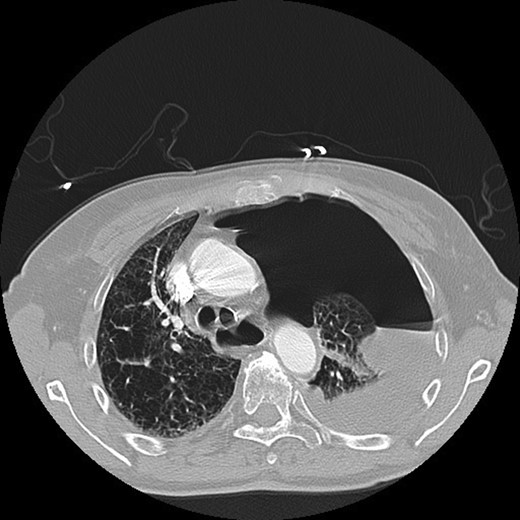

A 69-year-old female with Stage IV ovarian cancer status post-total abdominal hysterectomy, bilateral salpingo-oophorectomy, appendectomy, tumor debulking and eight cycles of carboplatin and paclitaxel presented with sudden onset of dyspnea. She reported a 4-month history of mild dyspnea and pleurisy, which had been attributed to previously diagnosed, cytology-proven bilateral malignant pleural effusions. She was also being treated for bilateral lower extremity Deep venous thromboses with warfarin. Computed tomography (CT) chest demonstrated a left hydropneumothorax with mediastinal shift (Fig. 1). Thoracostomy tube was placed with tea-colored drainage on insertion. She was intubated the following day for respiratory failure.

CT chest demonstrating left hydropneumothorax with mediastinal shift.